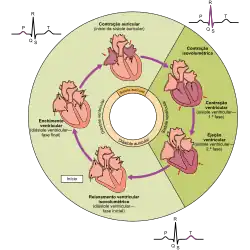

Ciclo cardíaco

O ciclo cardíaco denomina um batimento cardíaco completo, composto pela sístole, diástole e o momento de pausa.[9] O ciclo tem início com a contração das aurículas e termina com o relaxamento dos ventrículos. A sístole a é contração das aurículas ou dos ventrículos. A diástole é o relaxamento das aurículas ou dos ventrículos e o momento em que se enchem novamente de sangue. As aurículas e os ventrículos funcionam em conjunto. Quando os ventrículos se contraem durante a sístole, as aurículas estão relaxadas e a receber sangue. Quando os ventrículos estão relaxados durante a diástole, as aurículas contraem-se para bombear sangue para os ventrículos. Esta coordenação assegura que o sangue seja bombeado para o corpo de forma eficaz.[7]

No início do ciclo cardíaco, imediatamente antes da diástole, tanto as aurículas como os ventrículos se encontram relaxados. Como o sangue flui das áreas de maior pressão para as áreas de menor pressão, quando ambas as cavidades se encontram relaxadas o sangue flui para as aurículas. À medida que as aurículas se vão enchendo, a pressão aumenta de tal forma que o sangue flui para os ventrículos. No fim da diástole, as aurículas contraem-se, fazendo com que mais sangue flua para os ventrículos. Isto faz com que aumente a pressão nos ventrículos. Assim que os ventrículos atingem a diástole, o sangue é bombeado para a artéria pulmonar (no vaso do ventrículo direito) ou para a artéria aorta (no caso do ventrículo esquerdo).[9]

Quando as válvulas atrioventriculares (tricúspide e mitral) se encontram abertas para o sangue fluir para os ventrículos, as válvulas aórtica e pulmonar encontram-se encerradas de modo a impedir que o sangue regresse para os ventrículos. Quando a pressão ventricular é maior do que a pressão auricular, as válvulas tricúspide e mitral fecham-se. Quando os ventrículos se contraem, a pressão força as válvulas aórtica e pulmonar a abrir. Assim que os ventrículos relaxam, as válvulas aórtica e pulmonar fecham-se novamente em resposta à diminuição da pressão.[9]